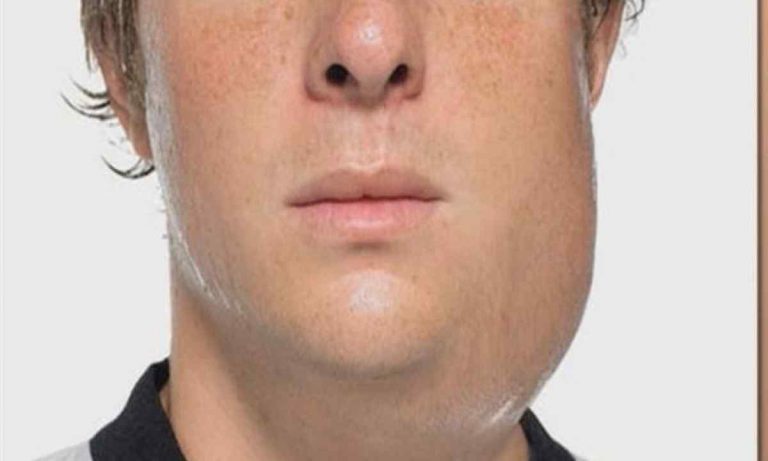

Набряклі щоки, що нагадують мордочку пухкого хом’яка, – ось як часто починається свинка, або епідемічний паротит. Цей...